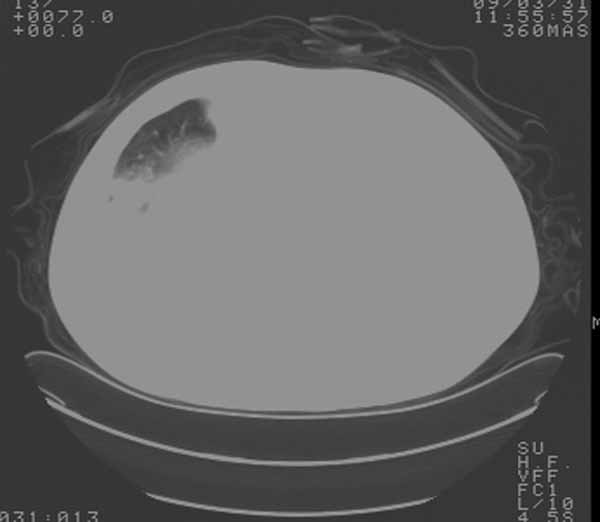

以下是引用余辉在2009-3-31 18:43:00的发言:[br]肺水肿,双侧心腔积液,心包积液,心影增大,疑似心衰

以下是引用wangyong1977在2009-3-31 20:46:00的发言:[br]肺水肿,双侧胸腔积液,心包积液,心影增大,疑似心衰 [br]

以下是引用宇宙ct在2009-3-31 18:57:00的发言:[br]肺水肿,双侧心腔积液,心包积液,心影增大,疑似心衰 [br] [br]